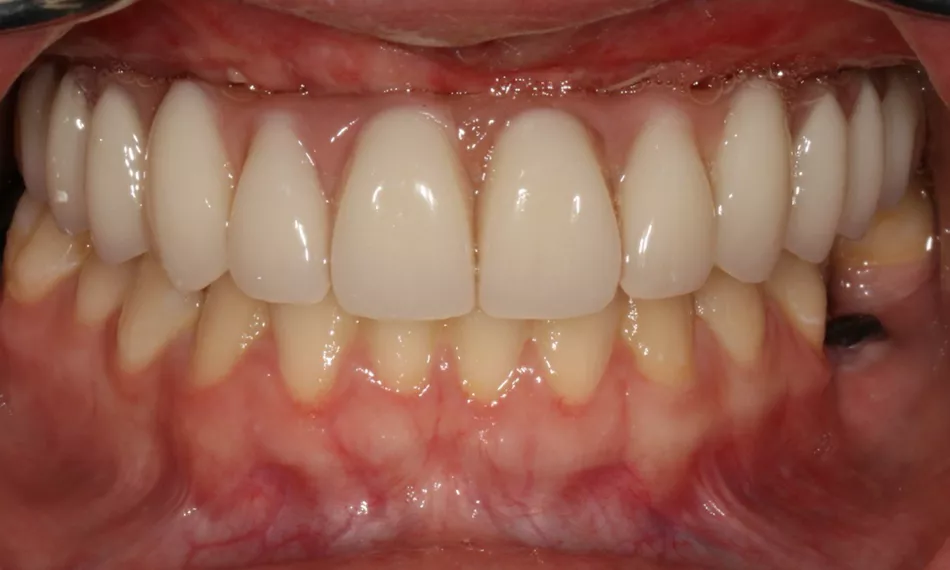

The final outcome of the treatment emphasizes the esthetic excellence of the zirconia monolithic prosthesis (Fig. 15), which blends seamlessly with the natural dentition. Its functional durability ensures long-term stability, providing both visual appeal and enhanced performance. This result has greatly improved the patient's overall satisfaction and quality of life.

Fig. 15

Additionally, lateral views taken at the end of the treatment offer a thorough perspective on the placement and fit of the prosthesis. These images confirm proper alignment with the surrounding tissues and occlusion, ensuring both functional performance and esthetic harmony, further contributing to the overall success of the treatment (Figs. 16,17).